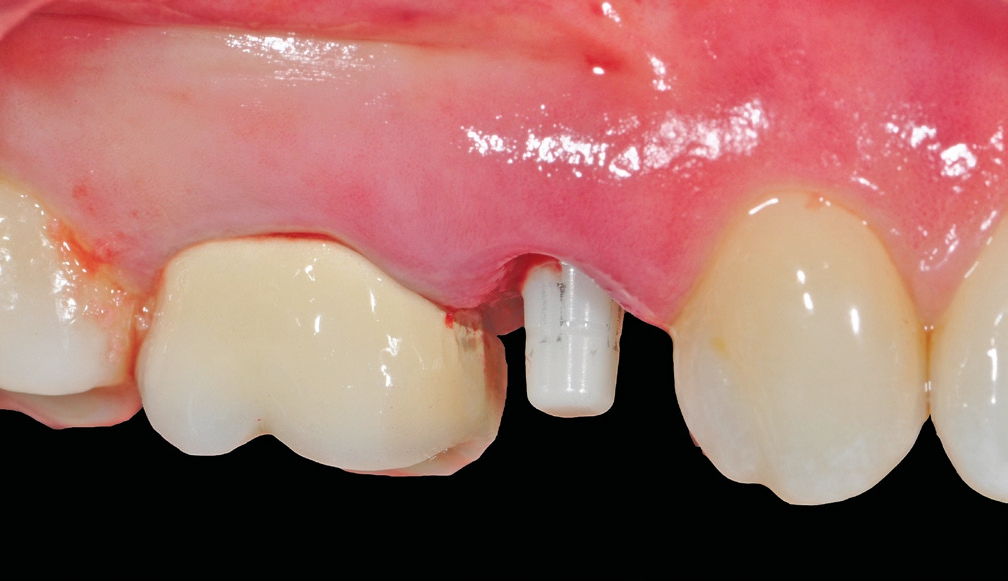

Implantatinsertion

Nach sorgfältiger Kürettage und Inspektion einer idealen Knochenalveole vom Typ I [11] konnte mit der Sofortimplantation begonnen werden. Die ersten beiden Pilotbohrungen wurden teilnavigiert mit der Bohrschablone durchgeführt. Das restliche Bohrprotokoll wurde nach den Vorgaben des Herstellers frei durchgeführt. Mit der Insertion des Implantats konnte die nötige Primärstabilität von 35 Ncm für eine sofortige provisorische Versorgung erreicht werden. Im Vorfeld war ein Situationsmodell der Ausgangssituation und darauf eine Tiefziehschiene vorbereitet worden, die jetzt für die intraorale Herstellung des Provisoriums mit fließfähigem Kompositmaterial verwendet wurde. Als stabilisierende Gerüststruktur diente dabei die präzise sitzende Einbringkappe (insertion.transfer) auf dem Implantatkopf, die zuvor auf die entsprechende Höhe eingekürzt worden war. Nach der Ausarbeitung und okklusalen Adjustierung der Krone wurde diese provisorisch zementiert.